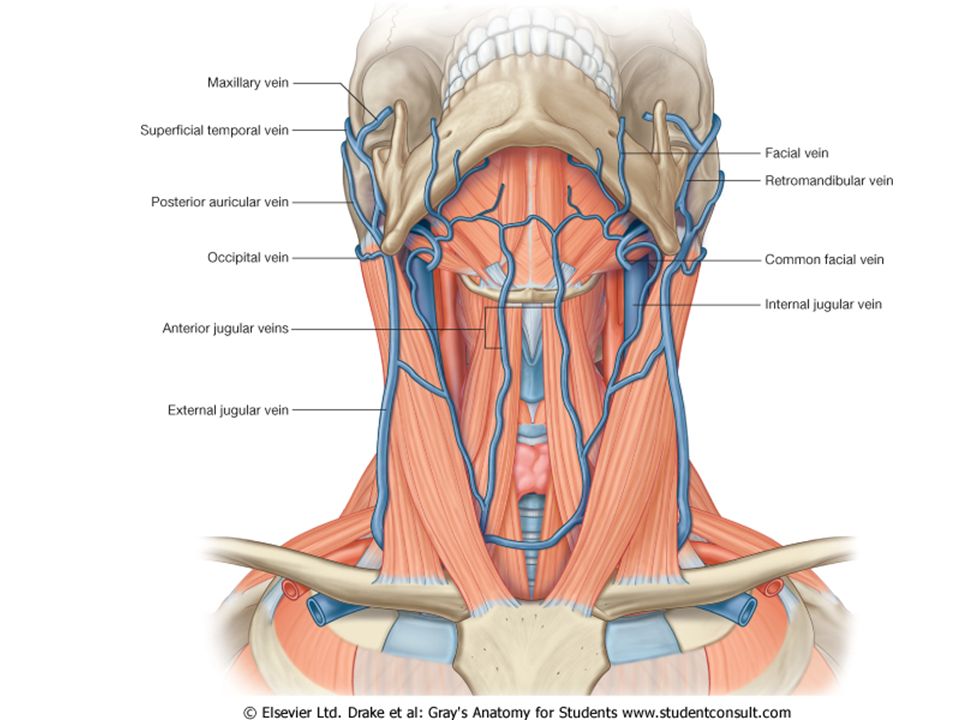

Анатомия внутренней яремной вены: КТ изображения